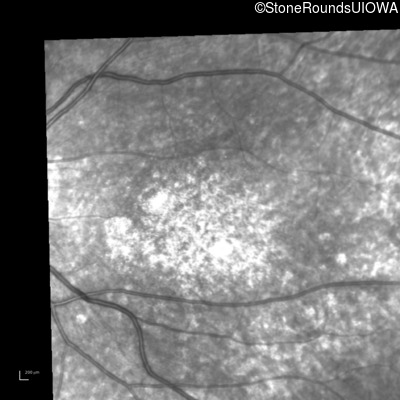

Infrared Fundus Photograph - Right - 10/160 -1 sc

Exemplar

Infrared Fundus Photograph - Left - 10/300 sc